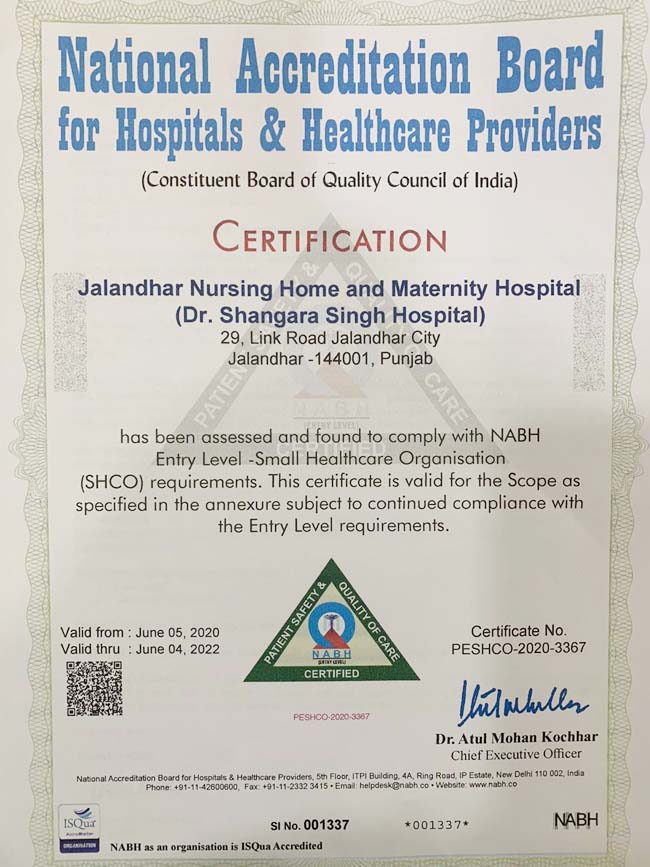

We are committed to providing high-quality medical care through advanced technology, experienced specialists, and a patient-first approach. Our hospital combines modern clinical practices with compassionate care to ensure safe, effective, and personalized treatment for every patient.

Our hospital is built on a foundation of clinical excellence, ethical practice, and patient satisfaction. With a team of highly qualified doctors and advanced medical infrastructure, we ensure accurate diagnosis, effective treatment, and compassionate care at every step of the healing journey.